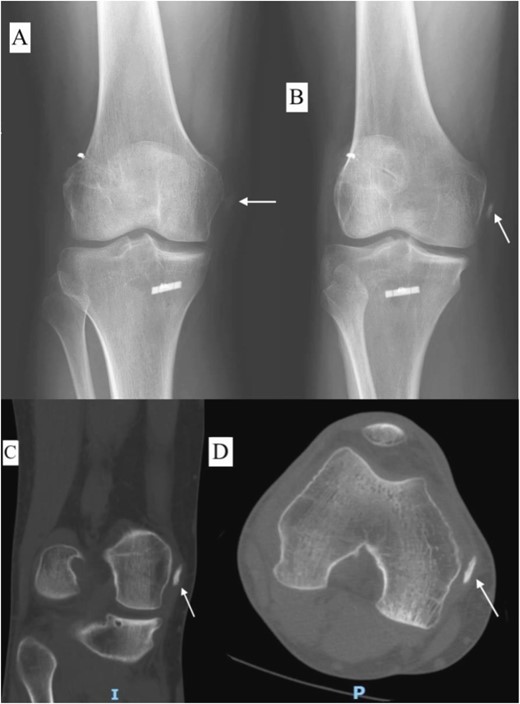

A 23-year-old male veterinarian presented to our out-patient department postright ACL reconstruction with hamstring autograft, PHMM tear by all-inside repair via sMCL pie-crusting technique, and lateral extra-articular tenodesis (modified Lemaire) in June 2023. A preoperative plain radiograph of the right knee revealed no evidence of HO (Fig. 1). No evidence of heterotopic ossification was detected in the right knee on plain radiographs taken 2 weeks postsurgery. (Fig. 2). Five months postsurgery, plain radiographs revealed new bone formation at the medial femoral condyle, precisely where the sMCL femoral origin was located (Fig. 3). The patient was asymptomatic and continued with rehabilitation. Seven months after the surgery, the patient started to complain of pain and clicking sensations when the right knee was flexed beyond an angle of 130°. Magnetic resonance imaging revealed consolidation of the newly formed bone, leading to a diagnosis of HO post-sMCL pie-crusting (Fig. 4). Nine months following surgery, the patient began to feel a bony mass on the medial side of the right knee. A plain radiograph and computed tomography (CT) scan revealed the complete formation of a bone island (Fig. 5). The past surgical history of this patient revealed that he had undergone left knee ACL reconstruction with hamstring autograft in December 2021, which failed and was complicated by a PHMM tear. The patient had presented to our facility for a revision. A revision ACL reconstruction was done using a bone-tendon-bone (BTB) autograft and PHMM tear all-inside repair via the sMCL pie-crusting technique in February 2022. A 2-year follow-up of the left knee, including physical examination and 3D-CT scans (Fig. 6), revealed no symptoms or signs of HO, although the same technique of sMCL pie-crusting was employed. Our patient suffered no head trauma during treatment. Past medical, drug, allergy, family, social histories, and reviews of systems were irrelevant to our case.

Plain radiograph of right knee AP (A), internal rotation AP (B), CT scan coronal view (C), and axial view (D) 9 months postoperative showing fully mature HO.